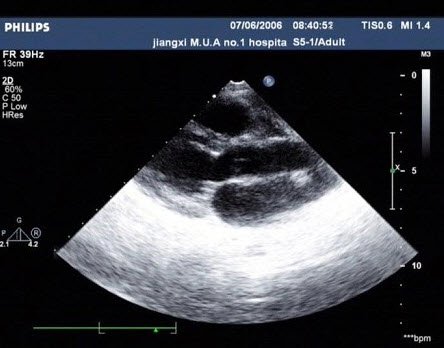

图为小儿超声心动图,根据此切面可以看到哪些腔室结构()

A.左房、左室、主动脉、右室、右房

B.左房、左室、主动脉、右室、右室流出道

C.左房、左室、主动脉、右室

D.左房、左室、右室、右房

E.左房、左室、主动脉、左心耳、右室、右房、右室流出道